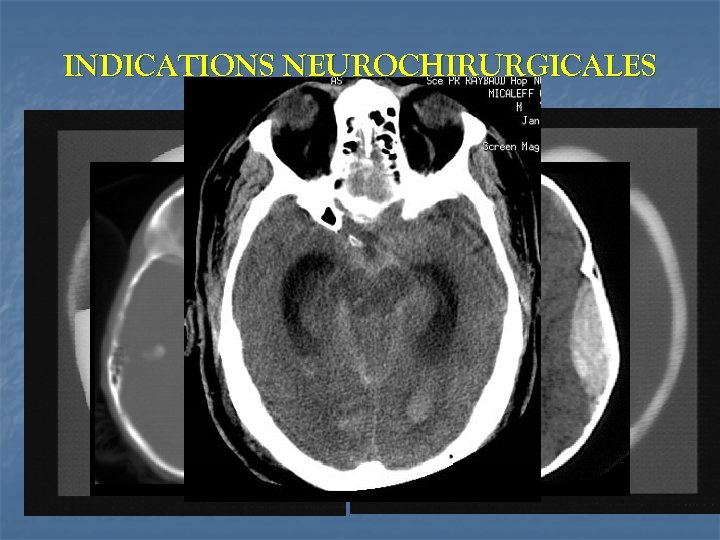

INDICATIONS NEUROCHIRURGICALES PRECOCES évacuation la plus précoce possible d’HED symptomatique évacuation HSD (> 5 mm avec déplacement >5 mm) drainage hydrocéphalie aiguë parage et fermeture des embarrures ouvertes hématome intra-cérébral, contusion hémorragique> 15 m. L+déplacement de la ligne médiane et oblitération des citernes de la base embarrure fermée compressive ( > 5 mm, déplacement de ligne médiane > 5 mm)

TDM n SIGNES A RECHER: ¯ ¯ œdème cérébral diffus, contusions et/ou hématomes intracérébraux, HED, HSD ¯ déplacement de la ligne médiane ¯ hémorragie intraventriculaire, sous-arachnoïdienne ¯ lésions axonales diffuses critères pronostiques: oedème cérébral, hémorragie intraventriculaire, déviation ligne médiane Fearnside(1993)

Classification des traumatismes crâniens d’après la Traumatic Coma Data Bank n n n Catégorie Lésion I Définition Pas de signe d’atteinte cérébrale à la TDM Lésion II Citernes de la base présentes, déviation de la ligne médiane < 5 mm et/ou absence de lésion hyperdense ou en mosaïque > 25 ml Lésion III Compression ou disparition des citernes de la base, déviation de la ligne médiane > 5 mm, absence de zone hyperdense ou en mosaïque > 25 ml Lésion IV Déviation de la ligne médiane > 5 mm, absence de zone hyperdense ou en mosaïque Lésion chirurgicale (hématomes) Pas de lésion chirurgicale ml, non chirurgicales Toutes lésions chirurgicales Lésions hyperdenses ou en mosaïque > 25